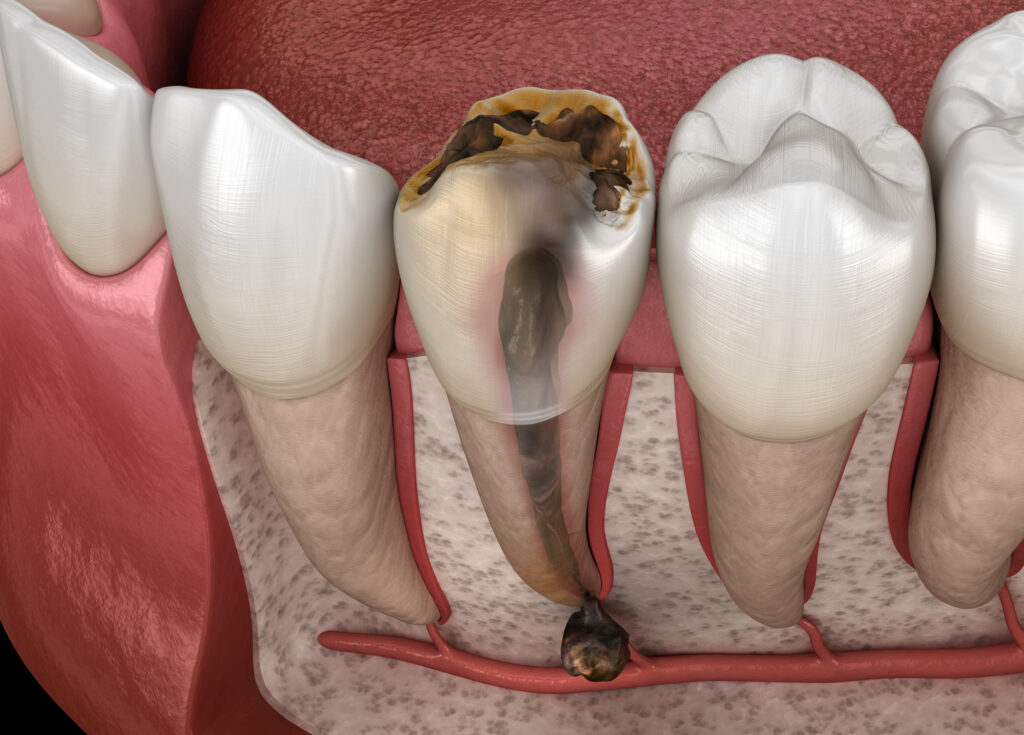

Root canal treatment treats infection in the centre of a tooth caused by bacteria that live in the mouth and invade the tooth. Infections can occur due to tooth decay, leaking fillings, or tooth damage.

The root canal system contains the dental pulp and extends from the tooth’s crown to the root’s end. The pulp is the nerve supply to your tooth. If it becomes infected, it can spread into the gum, causing an abscess or gumboil.

The bacteria will eventually spread down through the root tips and into your jawbone, causing a painful abscess and potentially systemic health issues. Ultimately, the tooth will die and will have to be extracted.